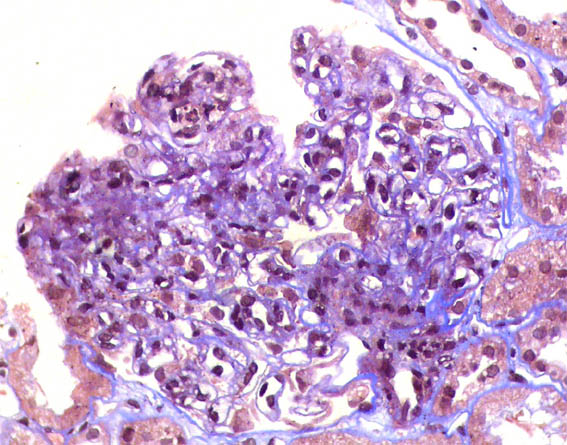

Figure 6. Masson's trichrome, X400.